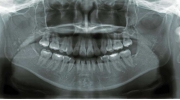

| マルチブラケット終了時

|